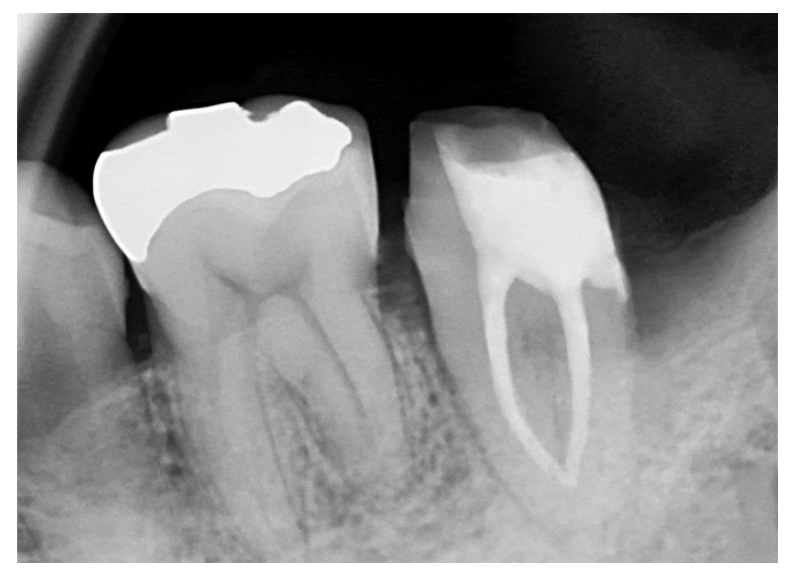

사랑니발치와 더불어

신경치료 및 잇몸치료까지

진행된 모습입니다.

다음 내원 시에는

제작된 보철물을 수복하면

치료가 마무리 됩니다!

또한 반대쪽 어금니도

치아를 살리기 위한 치료를

이어서 진행하기로 했습니다. ^^